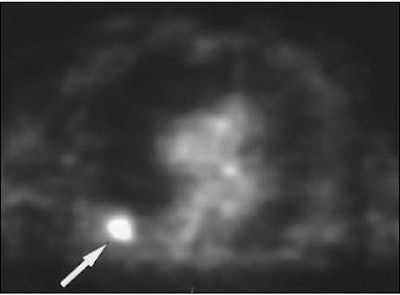

A 62-year-old man with a history of lung cancer and severe emphysema. CT scan (above) shows spiculated nodule (arrow) suggestive of either new primary tumor or recurrent disease. FDG-PET image (below) of thorax shows increased radiotracer uptake of FDG in nodule (arrow). Wedge resection was performed. Nodule was caused by atypical mycobacterial infection. Asad, S, Aquino SL, Piyavisetpat N, Fischman AJ, "False-positive FDG PET Uptake in Nonmalignant Chest Abnormalities," (AJR 2004 182; 983-989).